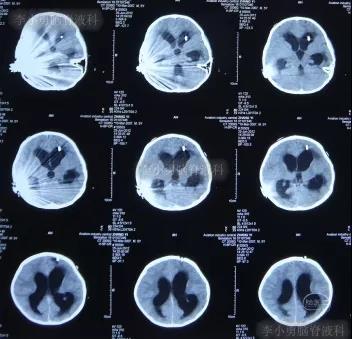

一到第3家医院,就开展了急诊气管插管和之后呼吸机辅助呼吸的抢救。住院次日,即2012年5月17日,脑CT检查并未发现明显异常(图-3)。

图-3:2012年5月17日耳蜗植入术后状态脑CT

住院3天根据腰椎穿刺脑脊液化验结果,确诊为肺炎链球菌脑膜炎,之后针对此细菌性脑膜炎的给以抗生素调整性治疗。

在利奈唑胺、头孢吡肟、利福平等药物抗炎治疗2周后,发热症状逐渐得到控制,意识也开始转清醒,但患儿自己示意有头痛症状;因腰穿未能抽出脑脊液,所以给予甘露醇处理,之后头痛可有缓解。在住院11天时即2012年5月27日(图-4)和住院14天时即2012年6月1日(图-5),分别进行过脑CT的检查,显示脑室有逐渐扩大的表现,但因为病情有所缓解,所以给以继续密切观察的处理。

图-4:2012年5月27日脑CT脑室稍扩大

图-5:2012年6月1日脑CT脑室稍扩大